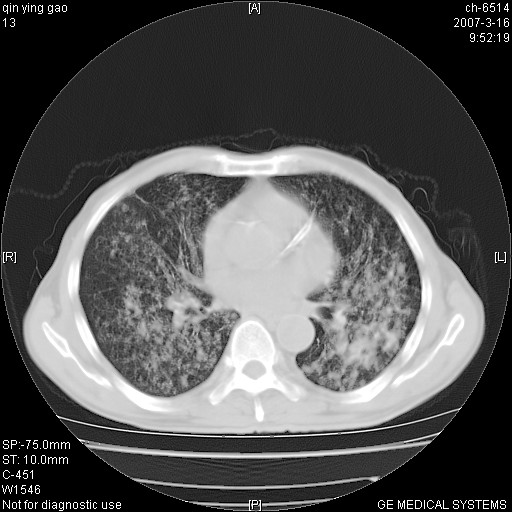

标题: CT7174:两肺弥漫性病变,请讨论

男,64岁.乏力2个月,畏寒、发热1月余。体重下降。血沉加快,白细胞不高。

两中上肺见有广泛新老不一的结节灶,并伴有纤维索条影,血沉加快,白细胞不高,首先考虑结核。

双肺可见大小不等结节状密度增高影,密度不均,分布不均(双肺上叶为著),亚急性血行播散性肺结核.

双肺以中上肺野为著斑片状.结节壮密度增高影,纵隔淋巴结无明显肿大。考虑:

(本例特征:以大小不等结节为主,主要分布在双上肺,并部分病灶融合成较大结节,期间搀杂诸多细小结节。从病灶特点与分布形式分析,更趋向于感染。)

男,64岁.乏力2个月,畏寒、发热1月余。体重下降。血沉加快,白细胞不高。 双肺可见大小不等结节状密度增高影,密度不均,分布不均(双肺上叶为著),亚急性血行播散性肺结核.

两中上肺见有广泛分布大小不一的结节灶及斑片状影,部分融合,双下肺未见异常密度影,纵隔无明显肿大淋巴结,血沉加快,白细胞不高,首先考虑结核。 建议结合ppd检查或痰培养排除其他非特异性炎症。

中上肺野密布棉团状影,以胸膜下区为界,边缘模糊,可能是小叶或腺泡渗出及实变。全肺野弥漫分布网线样影及细小粟粒样影,可能是细支气管炎及间质内炎症。综合分析应首先考虑气道播散性感染,而肺内多处斑点性钙化,强烈提示陈旧结核复发并支气管播散。建议详细讯问病史

病变以两肺上野为著,部分病灶有钙化,纵隔窗显示病灶有新老不一,这个首先和结核脱不了干系,还有部分病灶有融洽的倾向,肿瘤也不能完全排出